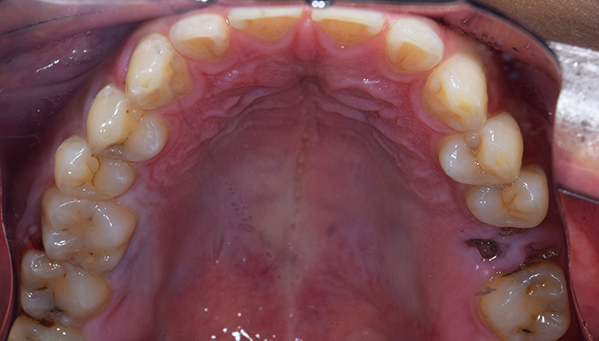

治療前:上の歯

担当医師所見:

臼歯部に残根状態の歯牙があり、またカリエス(虫歯)の散在が認められる。残根部分の両隣在歯は欠損部に対して傾斜し始めている。

治療後:上の歯

左上第1大臼歯は抜歯し、仮歯に置き換えた後治癒を待ちジルコニアBrで補綴。また右上第1大臼歯は根管治療終了後にジルコニアクラウンで補綴。前歯部は審美性を考慮しジルコニアボンドにて補綴した。 色調、形態共に調和がとれている。